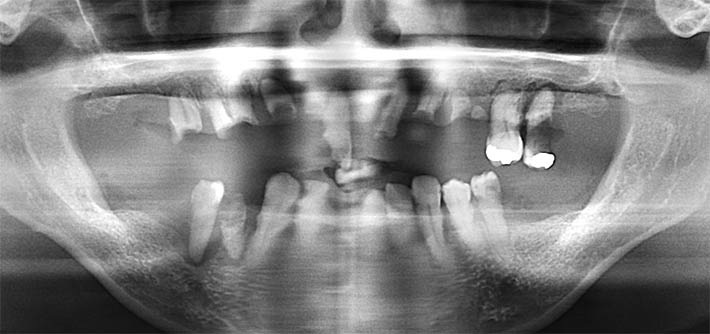

パノラマX線

全顎に渡り歯周病、カリエス(虫歯)、根尖性歯周炎等が進行し、歯を保存する事が困難である。